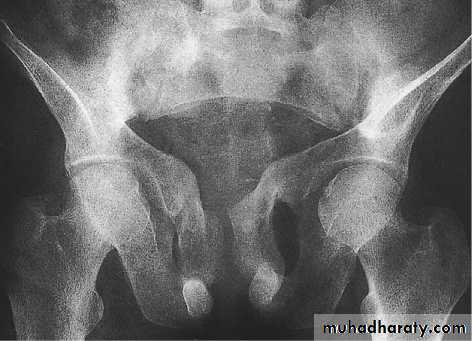

Excessive secretion of PTH.

May be primary , secondary, or tertiary.PTH- enhance calcium conservation resulting in hypercalcaemia and hypercalciuria and

Hyperphosphouria.Bone resorption manifest by ostitis fibrosa cystica and subperiosteal resorption.

hyperparathyroidism

Clinical features1- features of hypercalcaemia.

2-polyuria and renal disorders

3- bone pain and pathological fractures.